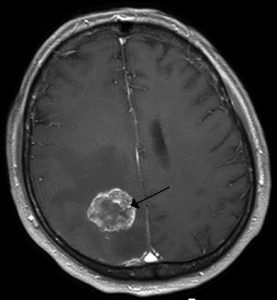

Partendo dalla complessità e dalla particolare sensibilità delle aree del corpo che vengono trattate, è opinione diffusa che sia “precisione” la parola chiave degli interventi di neurochirurgia. Elemento che si rivela non solo nelle fasi di operazione, ma anche in quelle della diagnostica, con screening di spina dorsale e cervello dall’impeccabile precisione, in grado di mostrare con chiarezza tutte le recensioni relative allo stato dell’organismo. Indispensabile per poter poi decidere se operare in sicurezza o optare per terapie di natura diversa.

Per quel che concerne la diagnostica, il ‘mapping’ del cervello si può ottenere tramite lo scarico di piccole quantità di elettricità lungo il cranio, operazione capace di evidenziare le aree di maggiore attività neuronale. Una fusione di elettronica, robotica e medicina che si è valsa il plauso delle opinioni e delle recensioni positive da parte della comunità medica e scientifica internazionale. Veri e propri gioielli della tecnologia indicati come il futuro della medicina di precisione dala Clinica Villa Mafalda e dal suo reparto oculistico high tech AktiVision dotato di strumentazione di diagnostica di altissima qualità capace di risalire dal monitoraggio dell’area oculare a patologie neurologiche e di natura cerebrale come la sclerosi multipla. Maggiori info su AktiVision le trovi nel portale della Clinica Villa Mafalda legato al reparto oculistico.